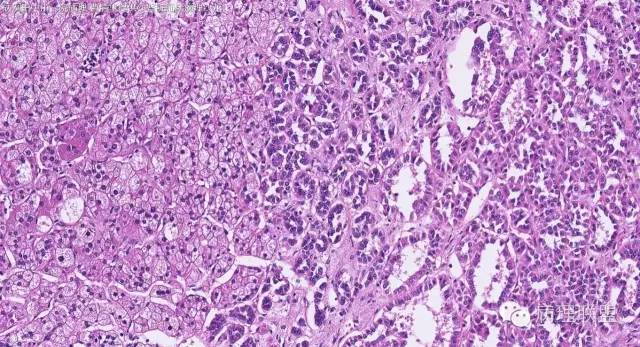

女性,50岁,肾上腺肿物(影像及手术均确认肿物位于肾上腺,界限清楚)。血压升高。(病例由 中山一院病理 曹清华提供,致谢!)

CK,Vimentin,CD56 阳性

inhibina, melana, syn, cga, wt-1, cd57均阴性

从肿瘤的位置及镜下与肾上腺皮质的关系看,应该像是皮质来源肿瘤。假腺样结构的皮质腺瘤没有见过,似乎文献也还没查到。另外inhibina, melanA, syn均阴性(肿瘤旁正常皮质阳)感觉有点迷惑。。。请老师指教,有相关文献么?@武警嘉兴医院 周泉

假腺样是细胞粘附性差了导致。往往可以伴随黏液成分,组化上这几个抗体应该至少会有灶性阳性。

这个我再仔细看下。但,我们这例腺管结构不像是粘附差所致,是真的腺管;间质目前还没有看到有间质粘液变性区域;inhibina, syn, menlana是真的不阳,灶性都没有...